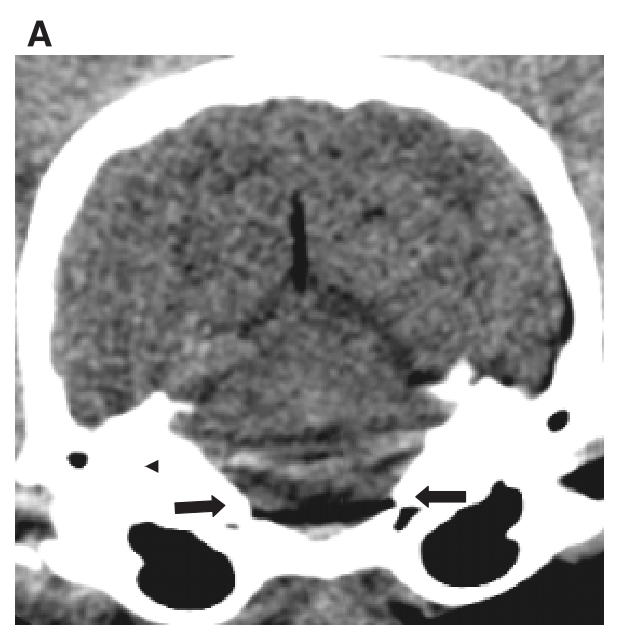

What is this artifact and how is it fixed?